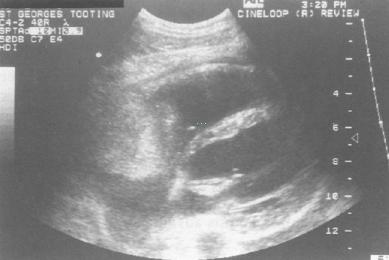

A previously healthy 24-year-old man presented to his General Practitioner with a short history of a dry cough and shortness of breath on exertion. Subsequent chest-radiography showed a markedly enlarged, globular cardiac silhouette, and transthoracic echocardiography showed a massive pericardial effusion and a large right atrial mass. A pericardial drain was inserted yielding over four litres of heavily blood-sustained fluid. Cytological examination revealed that the fluid contained abundant lymphocytes although immuno-phenotypic markers indicated that these were a normal inflammatory population of B- and T-cells with no evidence of clonatity. No malignant cells were seen and no microbial growth was obtained from the fluid after prolonged culture. Further investigation with transoesophageal echocardiography, computed tomography (CT) and magnetic resonance imaging (MRI) demonstrated that the mass infiltrated the free wall of the right atrium and extended around the aortic root and pulmonary trunk. There was no obstruction of either the superior or inferior vena cava (Fig. 1). MRI scan showed additional evidence of possible metastatic deposits in four vertebral bodies, although these were not apparent on either CT or isotope bone scan. The appearances of the mass were consistent with an angiosarcoma but histological confirmation was required. Transvenous biopsy was performed using a catheter bioptome (Cordis biopsy forceps) following localization of the tumour angiographically using contrast injected into the right atrium. Unfortunately the tissue obtained proved nondiagnostic despite taking multiple biopsies on two separate occasions and approaching the mass using the right femoral and right subclavian venous routes. Previous experience in our own institution suggests that open surgical biopsy of these highly vascular tumours is hazardous, and it was therefore decided to perform a percutaneous FNA under ultrasound guidance. Using an aseptic technique the right atrium was imaged in an oblique plane from the subxiphisternal region and a route plotted for the needle (Fig. 2). Under ultrasound guidance a 21 gauge

Fig. 1 Ultrasound image showing an echogenic mass lying within the right atrium.

Fig. 2 - The dotted line was used to assess depth of biopsy and to plan

the course of the needle through the right atrial wall, the atrial cavity

and into the mass. A picture of the needle in the mass was unfortunately

not obtained.